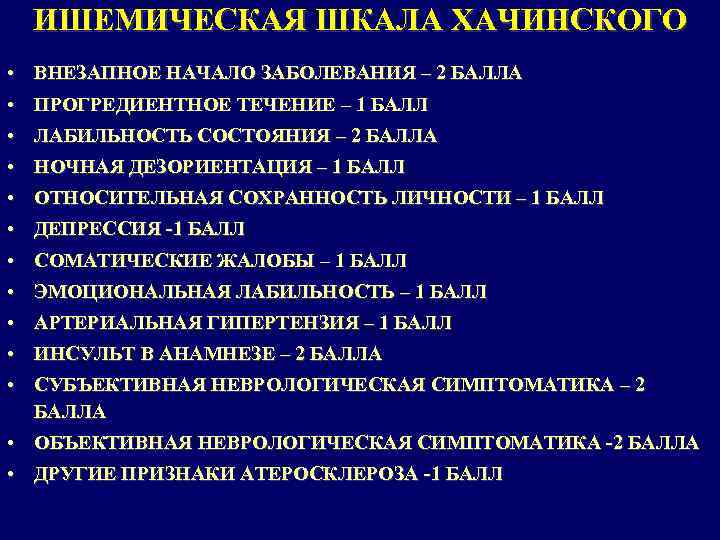

ИШЕМИЧЕСКАЯ ШКАЛА ХАЧИНСКОГО • ВНЕЗАПНОЕ НАЧАЛО ЗАБОЛЕВАНИЯ – 2 БАЛЛА • ПРОГРЕДИЕНТНОЕ ТЕЧЕНИЕ – 1 БАЛЛ • ЛАБИЛЬНОСТЬ СОСТОЯНИЯ – 2 БАЛЛА • НОЧНАЯ ДЕЗОРИЕНТАЦИЯ – 1 БАЛЛ • ОТНОСИТЕЛЬНАЯ СОХРАННОСТЬ ЛИЧНОСТИ – 1 БАЛЛ • ДЕПРЕССИЯ -1 БАЛЛ • СОМАТИЧЕСКИЕ ЖАЛОБЫ – 1 БАЛЛ • ЭМОЦИОНАЛЬНАЯ ЛАБИЛЬНОСТЬ – 1 БАЛЛ • АРТЕРИАЛЬНАЯ ГИПЕРТЕНЗИЯ – 1 БАЛЛ • ИНСУЛЬТ В АНАМНЕЗЕ – 2 БАЛЛА • СУБЪЕКТИВНАЯ НЕВРОЛОГИЧЕСКАЯ СИМПТОМАТИКА – 2 БАЛЛА • ОБЪЕКТИВНАЯ НЕВРОЛОГИЧЕСКАЯ СИМПТОМАТИКА -2 БАЛЛА • ДРУГИЕ ПРИЗНАКИ АТЕРОСКЛЕРОЗА -1 БАЛЛ